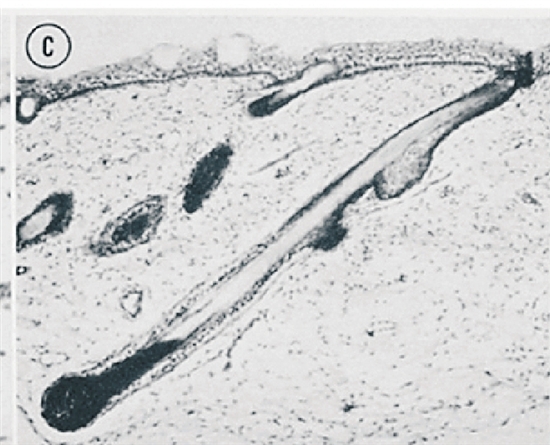

而这一阶段,也恰好是头皮毛囊向下生长的时期。当原始的毛囊在向头皮深处探入时,头皮恰好在像吹气球一样缓慢扩张,这样一来,头顶后方那圈张力最大的头皮上,本该垂直生长的毛囊就被扩张的头皮“带歪”了(见下图)。毛囊顺着张力曲线形成了螺旋状的规律倒伏,而头发生长的方向也因此发生改变,变成了终生不会再变化的“发旋”。

胎儿头顶后方头皮中毛囊的发育过程。图A为10周,图B为16周,图C为 18周。随着毛囊的向下生长,毛囊逐渐愈加倾斜。论文作者推测这一改变由皮肤受到牵拉所导致。